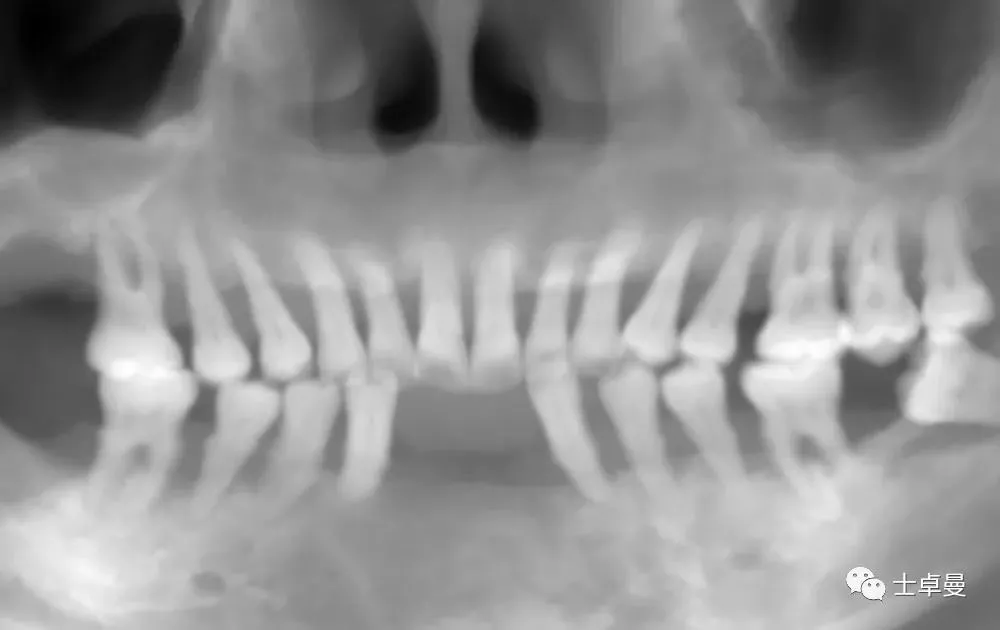

影像学检查

· CBCT检查:显示口内余留牙牙槽骨吸收至根尖1/3;

· 上颌双侧后牙区上颌窦底可用骨高度不足;

· 下颌双侧后牙区下颌神经管上方可用骨高度不足。